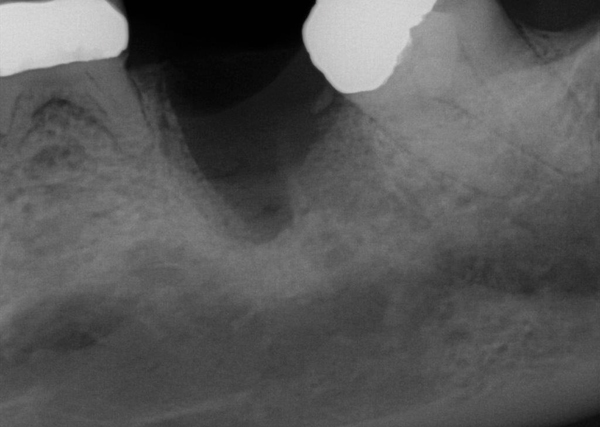

Fig 15. (Case 3) Radiograph of tooth No. 19, which had a hopeless prognosis.

Figure 15

Fig 16. Radiograph of extraction socket. Buccal and lingual plates were defective.

Figure 16